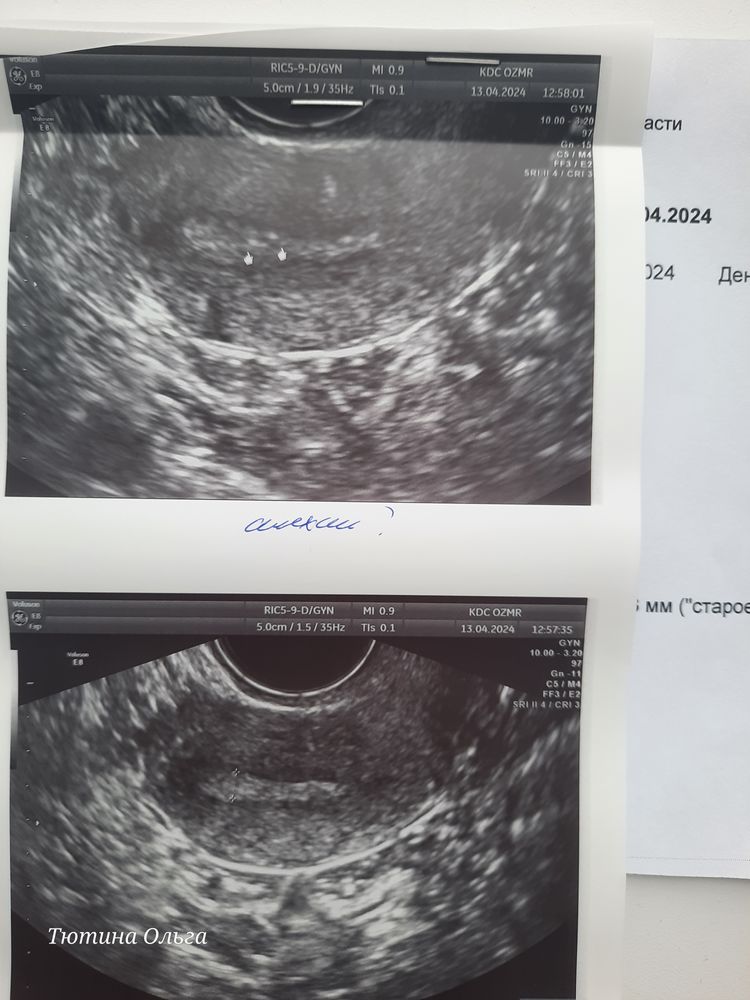

Синехии в матке

MariNka, самое интересное, что узи делала три месяца назад никто ничего не увидел что-ли... вот как там возможно... один увидел другой не смотрит.